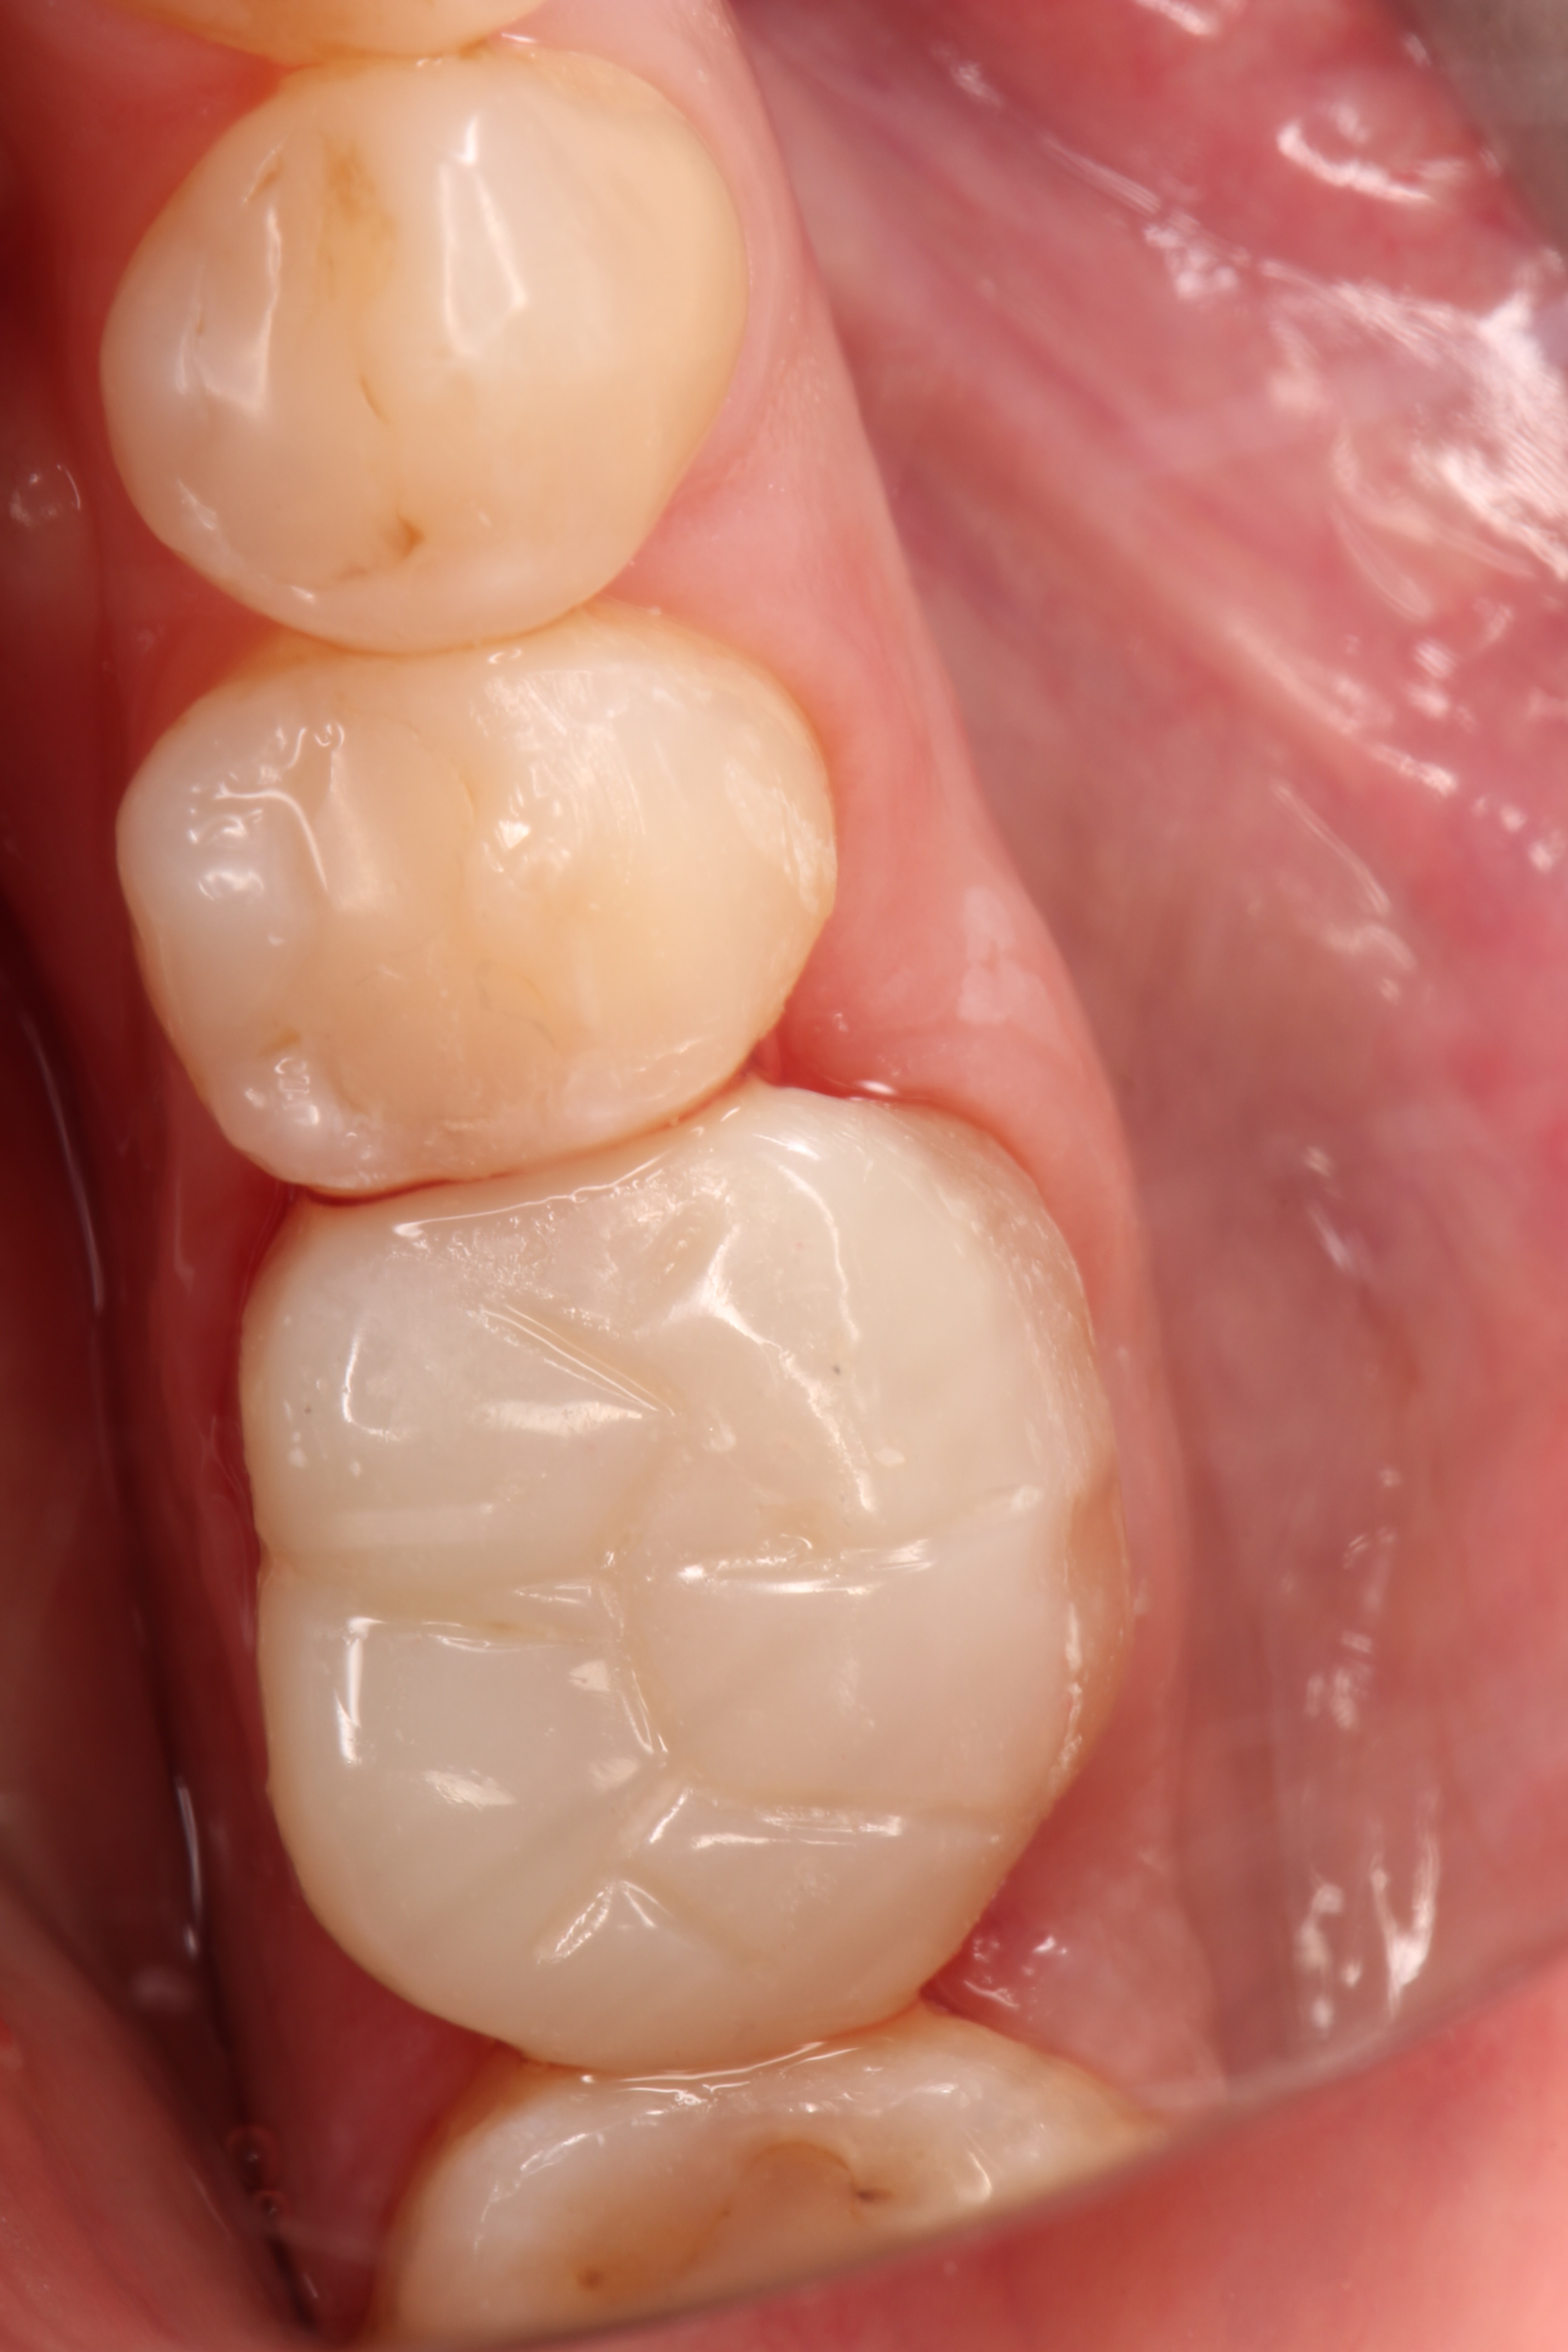

Crowns and onlays by Professor Brian Millar

This course solidified my knowledge and allowed me to practice various cuspal coverage treatments including overlays, onlays and vonlays. I was able to learn about the different preparation techniques and margins required for each indirect material.